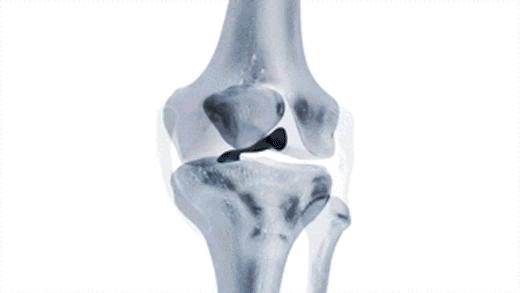

但是在膝关节活动的时候,偶尔会发生半月板撕裂部位的反折,造成瞬间的卡压,患者会表现出明显的打软腿以及比较明显的疼痛,之后需要休息一段时间,缓慢的屈伸膝关节慢慢的才会恢复正常。这种情况说明卡住的撕裂部位,又恢复了常态。(大家看下面这个动图,如果这个破裂的瓣比较大,那么就有可能发生反折和卡别)

还有一种半月板的问题有可能会诱发患者出现打软腿或者是关节的卡片,那就是盘状软骨。这种情况是先天性的变异,正常应该是月牙状的半月板,发育成了满月,形态上看起来像一个盘子,这种情况就容易发生撕裂,诱发患者出现打软腿和疼痛。(下图即为盘状半月板的影像学资料)